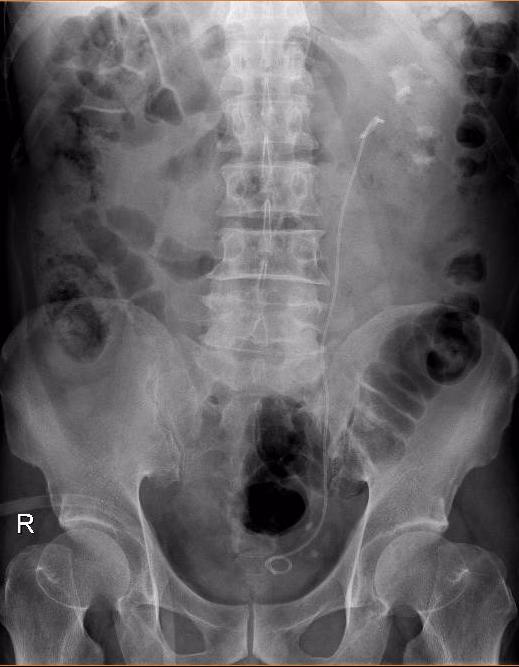

图片1.jpg

KUB见肾结石大,DJ管位置良好